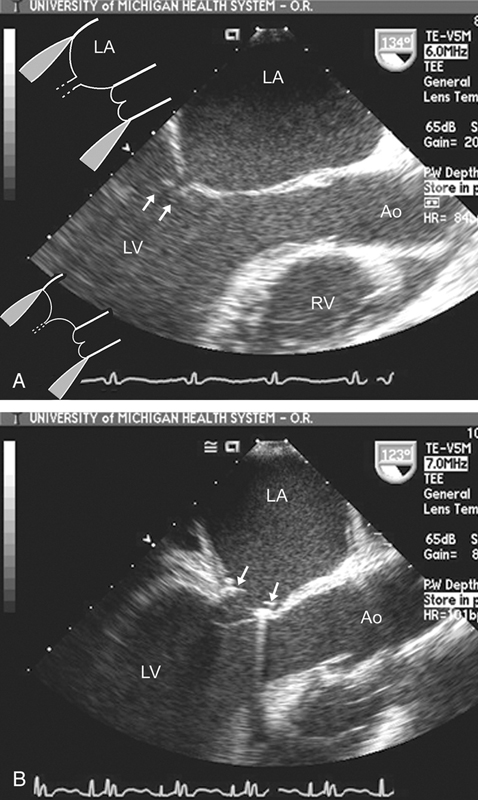

فحوصات تشخيصية لبعض امراض القلب والشرايين التاجية